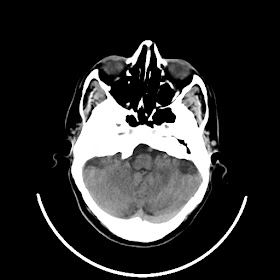

39 years old man with chronic alcoholic since 17 years.

& cough with cold & dark colour stool.

Now feeling weakness & dimness of vision.

O/E images: